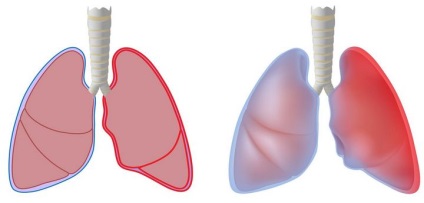

- Probleme ale cailor respiratorii (emfizem, tuberculoza pulmonară);

Prea târziu pentru tratament pentru îngrijiri medicale, precum și un tratament analfabet selectat poate fi complicații extrem de grave, care duc la moarte. Printre ei - revărsat pleural, sepsis, empiem, sindrom de detresă respiratorie, insuficiență respiratorie acută, miocardita.

O complicație gravă a pneumoniei - formarea bășicilor și abcese. starea pacientului se poate deteriora rapid, există astfel de fenomene ca febra foarte mare, scăderea tensiunii arteriale, tuse cu spută urat mirositoare.

Această condiție trebuie tratată chirurgical, până la pulmonectomy, după care calitatea vieții este redusă în mod semnificativ. Cât de mulți oameni pot trăi cu această condiție a provocat pneumonie? Din păcate, moartea are loc în doar câțiva ani.

pneumonie de aspirație are loc atunci când inhalarea conținutului gastric. Este provocat microflorei aerobe Gram-negativ. Severitatea stării este exacerbată de faptul că sucul gastric intră în căile respiratorii, provocând o arsură chimică a mucoasei. Este posibil ca omul a murit de pneumonie acest tip? Rata de mortalitate este destul de mare, mai ales în cazul aspirației cronice.